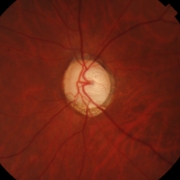

緑内障治療に精通した専門医が3名在籍し、病状や進行度に応じた最適な治療をご提案します。早期発見・早期治療を重視しています。

緑内障や黄斑疾患との併発症例など、難症例にも対応しています。